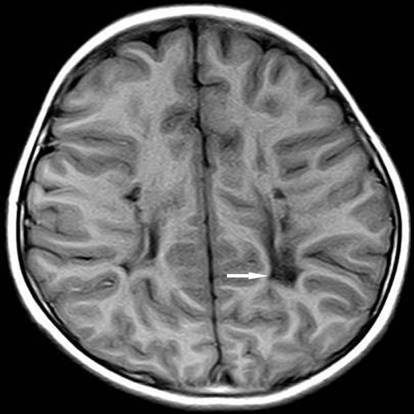

小兒腦癱的發(fā)病原因主要是母親分娩時(shí)困難,引起胎兒窒息或顱內(nèi)出血,出生后不呼吸、腦缺氧時(shí)間較長(zhǎng)所致。也有一部分是新生兒后天高燒、腦炎、腦膜炎等的后遺癥。小兒腦癱臨床上分為五種類型:

2、痙攣型腦性癱瘓 是最典型和常見的類型醫(yī)|學(xué)教育網(wǎng)整理。主要表現(xiàn)以雙下肢為主的痙攣性截癱獲四肢癱瘓?;純盒凶?、站立困難,走路足尖著地呈剪刀步態(tài)。肌張力明顯增高,腱反射亢進(jìn),可有病理反射。常伴有語言及智能障礙。

4、手足徐動(dòng)型腦性癱瘓 多由核黃疸、新生兒窒息引起的基底核損害而發(fā)病。患兒表現(xiàn)為面、舌、唇及軀干肢體的舞蹈樣或徐動(dòng)樣動(dòng)作。伴有運(yùn)動(dòng)障礙和肌張力增高。